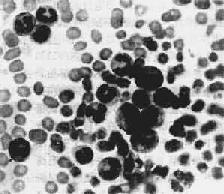

图11-7 慢性粒细胞性白血病 周围血内白血病细胞主要为中幼粒细胞 2.骨髓 CML时骨髓增生活跃,各期粒细胞均可见到,以中、晚幼粒和杆状粒细胞占优势,幼红细胞和巨核细胞早期可增生,血小板增多,晚期则被抑制。CLL骨髓内淋巴细胞增多,可呈结节状或弥漫性浸润,主要为成熟的小淋巴细胞,原及幼淋巴细胞很少。粒、红、巨核细胞系及血小板均减少。 3.淋巴结 CLL时淋巴结明显肿大。早期淋巴结可活动,晚期瘤细胞浸润包膜,肿大的淋巴结常相互融合,并与周围组织粘连。切面灰白色鱼肉状。镜下可见淋巴结内有大量瘤细胞浸润,严重者淋巴结构破坏消失。CML时淋巴结轻至中度肿大,不如CLL明显。 4.脾 脾多明显肿大,CML最显著,可达4000~5000g。肿大的脾占据腹腔大部,甚至可达盆腔。红髓脾窦内有大量白血病细胞浸润,可压迫血管引起梗死。CLL时,脾肿大不如CML时严重,一般不超过2500g。肿大的脾包膜增厚,常有纤维性粘连,质较硬,切面暗红色,脾小体不明显,呈均质状。镜下见大量白血病细胞浸润,CLL时主要累及白髓,严重者白血病细胞弥漫浸润,脾小体和脾髓结构消失。 5.肝肝中度肿大,表面光滑。镜下,各型白血病的浸润方式不同。CLL时,瘤细胞多浸润于汇管区及其周围;CML时,瘤细胞多沿肝窦呈弥漫性浸润。 此外,慢性白血病时,白血病细胞并常浸润胃肠、心、肾、皮肤等全身器官和组织。白血病细胞浸润处可破坏相应的组织和器官而引起出血、感染等继发性变化。 慢性白血病病变发展缓慢,病程较长。开始约2~3年病情稳定,对化疗有效,有时稳定期可达10年以上。以后治疗无效,病情加重。CML最后常发生急性变,突然出现原因不明的高热,脾迅速肿大,贫血、血小板减少,出血症状加剧,骨及关节疼痛,骨髓和血中原粒和早幼粒细胞突然增加。急性变发生后病情常急转直下,预后很差。CLL发生急性变者极少。CLL患者平均寿命比CML长,最后多因低丙种球蛋白血症,免疫功能低下并发感染而致死。 【类白血病反应】 类白血病反应(leukemoid reaction)通常是由于严重感染、某些恶性肿瘤、药物中毒、大量出血和溶血反应等刺激造血组织而产生的异常反应,表现为周围血中白细胞显著增多(可达50,000/μ1以上),并有幼稚细胞出现。类白血病反应的治疗和预后均与白血病不同。一般根据病史、临床表现和细胞形态可以与白血病鉴别,但有时比较困难。类白血病反应有以下特点可协助鉴别:①引起类白血病反应的原因去除后,血像可恢复正常;②类白血病反应时,一般无明显贫血和血小板减少;③类白血病反应时,粒细胞有严重毒性改变,胞浆内有毒性颗粒和空泡等;④类白血病反应时,中性粒细胞的碱性磷酸酶活性和糖皆明显增高,而粒细胞白血病时,两者均显著降低;⑤慢性粒细胞白血病细胞内可见Ph1染色体,类白血病反应时则无。

二、慢性白血病慢性白血病起病缓慢,病程长,早期多无明显症状。有些病人在体格检查或因其他疾病就诊时发现。主要症状为乏力、消瘦、发热、脾肿大等。 慢性白血病按细胞来源分为慢性粒细胞白血病(CML)和慢性淋巴细胞白血病(CLL)。 CML来源于多能髓样干细胞。瘤细胞的成分以幼粒细胞为主。骨髓和脾内幼稚粒细胞明显增多。与急性白血病不同,CML时髓样干细胞仍具有分化成熟的能力,周围血内可见大量成熟的粒细胞。原始粒细胞的异常增生与分化,可能与干细胞对调节造血细胞生长分化的反馈信号反应不足有关。 CML病人中约90%伴有一种染色体异常,称为Ph1染色体,已确定为CML的标记染色体。Ph1染色体指22号染色体的长臂易位至9号染色体长臂。Ph1染色体的存在与CML的发生发展有关。典型的CML时Ph1阳性,多见于青壮年,化疗效果好。Ph1阴性的CML多见于老人和小儿,预后不佳。 CLL为小淋巴细胞恶变而来。绝大多数CLL来源于B细胞,T细胞性CLL很少见。恶变的B细胞无免疫功能,不能转化为浆细胞,病人常有低丙种球蛋白血病。有时CLL与小淋巴细胞淋巴瘤不易区别。 【病理变化】 1.周围血像周围血白细胞显著增多,数量正常或减少者少见。CML时白细胞增多尤为明显,多在10万~至80万/μ1之间,少数甚至可超过100万,其中大多数为较成熟的中、晚幼和杆状核粒细胞,早幼粒和原粒细胞很少(图11-7)。嗜碱性和嗜酸性粒细胞也增多。CML时中性粒细胞内碱性磷酸酶常缺如或降低。这点有助于与类白血病反应相区别。CLL血白细胞总数多在3万~10万/μ1之间。血像单一,绝大多数为成熟的小淋巴细胞,只有少数幼淋巴细胞。慢性白血病早期贫血较轻,血小板无明显减少。CML时血小板常增多。晚期有明显贫血和血小板减少。